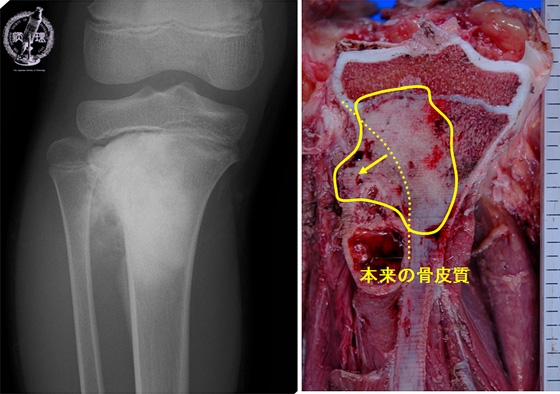

- ★(6)Osteosarcoma

X-ray finding (Left) and macroscopic view (Right): X-ray shows irregular bone destruction and sclerosis. It is concordant with macroscopic view, with destruction of cortical bone and grayish white solid tumor extending into the soft tissue.